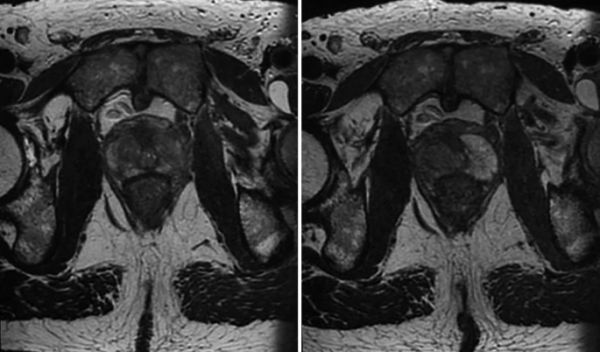

用于前列腺癌的 IRE 具有良好的耐受性,并且在手术前后的泌尿、肠道、身体和精神评分方面具有可比性。这与前列腺段消融无关 [ 20 , 21 ]。冈瑟等人。报告了超过 471 名患者接受局灶性局部疾病或高风险或抢救治疗的结果。没有观察到尿失禁,性功能下降是一种短暂的影响,12 个月后只有 3% 的残余勃起功能障碍。已经确定了基线时的性功能、患者年龄和结果之间的关系。最低的术前性状态对应于性保存方面较差的结果 [ 15 , 22 ]。 通过 PSA、影像学和再活检评估前列腺 IRE 的肿瘤学结果。对局灶性/偏侧切除术和全腺体切除术的最大回顾性研究发现 6 年的无复发生存率为 90%,这使得 IRE 与根治性前列腺切除术的结果相当 [ 15 ]。 成像最好通过对比增强超声或 MRI 进行,与前列腺切除标本相比,这两种技术都可以可靠地估计消融体积和位置 [ 23 ](图 16.6 和 16.7 )。 图 16.6

IRE 前(左)和 6 周后(右)前列腺右后叶的 MRI 图像。靶区体积大,右叶缩小。T2 加权图像